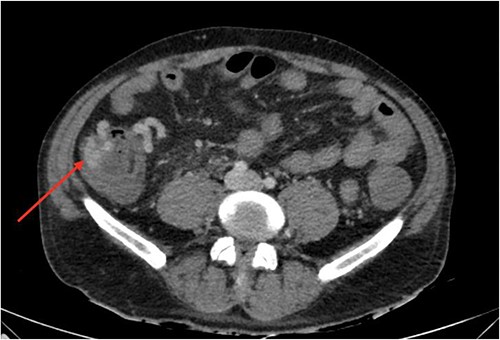

On gastroscopy, neither bleeding sources nor features of portal hypertension were identified. Subsequently, a large volume rectal haemorrhage occurred, resulting in severe hypotension and syncope. The patient was resuscitated appropriately and received a massive transfusion protocol. A CT angiogram revealed focal clustered varices travelling retroperitoneally abutting the caecal pole (Fig. 1), which communicated with a large branch of SMV in the right iliac fossa (Fig. 2).

Sagittal view of computerized tomography imaging in portal venous phase with arrow marking varices at the caecum.